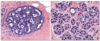

what are the two main microscopic features of comedo ductal carcinoma in-situ

pleomorphic, high grade nuclei central necrosis

what is the other name for large cell ductal carcinoma in-situ

comedocarcinoma

which, comedo or non-comedo ductal carcinoma in-situ, is more likely to progress to carcinoma

comedo